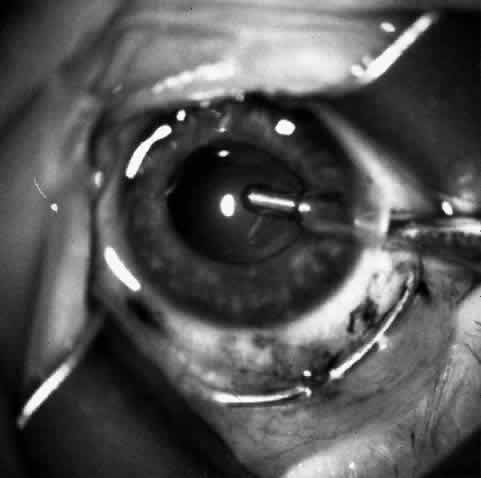

Children who have traumatic cataracts with corneal lacerations are well served by this procedure because the injury often destroys the capsular support that can be used to stabilize an intraocular lens.16–18 The epikeratophakia graft provides structural support for the weakened cornea and minimizes the induced irregular and regular astigmatism, in addition to correcting the optical error (Figs. 3 AND 4).

Fig. 4. Same patient as in Figure 11, with epikeratophakia lenticule in place 3 months after surgery. (Morgan KS, Ellis GS, Marvelli TL, Arffa RC: Epikeratophakia in children. with traumatic cataracts. J Pediatr Ophthalmol Strabismus 23:108–113, 1986)